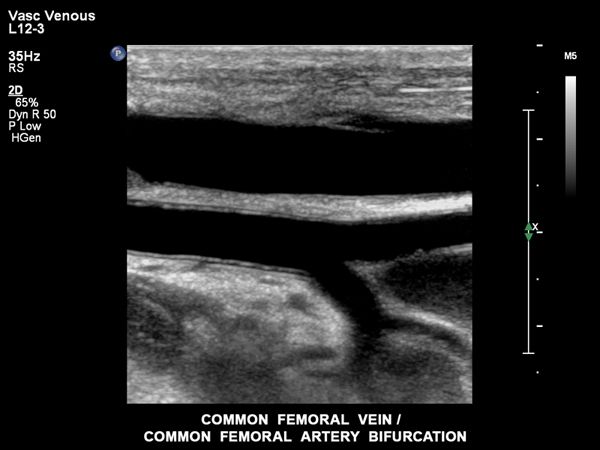

Philips ist bekannt für seine Expertise in Sachen Bildgebungstechnologien und hat mit nSIGHT eine revolutionäre neue Bildgebungstechnologie und eine völlig neue Methode zur Erstellung von Ultraschallbildern entwickelt, die folgende Möglichkeiten bietet:

- Besonders detaillierte Ultraschallbilder und eine außergewöhnliche zeitliche Auflösung

- Fähigkeit, Gewebehomogenität auf einer ganz neuen Ebene zu erkennen, ohne die Notwendigkeit der kritischen übertragenen Fokuszonenplatzierung

- Außergewöhnliche Penetration bei höheren Frequenzen für eine hervorragende Bildgebung bei schwierigen Patienten